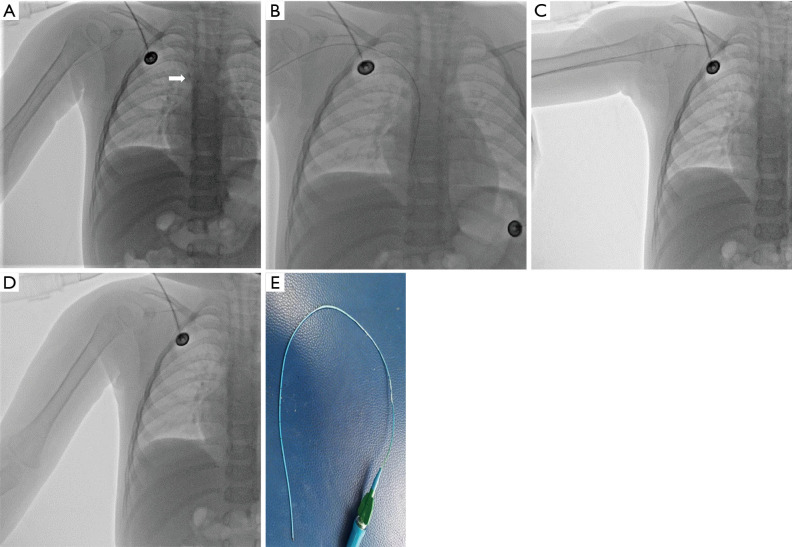

Case description: Three cases of difficult PICC removal were all children with acute lymphoblastic leukemia (ALL). All cases were male, range 3-6 years, mean 5.00±1.73 years, catheter indwelling time 289-433 days, mean 367.33±72.83 days. All three cases underwent PICC intubation via the basilic vein approach and all catheters were 3.0 French (Fr), silicone, single-lumen PICCs (Bard Access Systems, Inc., Salt Lake City, UT, USA). Removal of the PICC at the end of the treatment course was difficult. The pullback of the catheter went smoothly for the first few centimeters, but then resistance was encountered. The catheter did not move backward at that point, although we applied strong continuous traction. Several noninvasive approaches to remove the catheter (e.g., repositioning of the extremity, application of hot compress, and vascular massage) were all with no success. Eventually, the firmly adherent PICC was removed using fluoroscopy-guided guidewire-assisted technique in hybrid operating room safely and successfully.

Conclusions: Difficult PICC removal can result after prolonged dwell times. When conventional noninvasive interventions are unsuccessful, fluoroscopy-guided guidewire-assisted technique is a safe and effective method for the removal of adherent PICC.